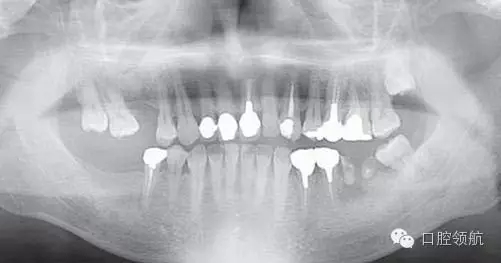

患者,38歲,男性,作為需要全面治療的患者來院?;局委熀?,右下頜磨牙區(qū)及右上頜磨牙區(qū),還有拔牙后的左下頜磨牙缺損區(qū),擬進行種植修復。圖1為初診時的曲面斷層影像,問診,模型診斷,曲面斷層檢查均未見異常,因此,最先在右下頜磨牙缺損區(qū),繼而在右上頜磨牙缺損區(qū)植入種植體,這些種植體愈合良好。

圖1 初診時的曲面斷層影像。